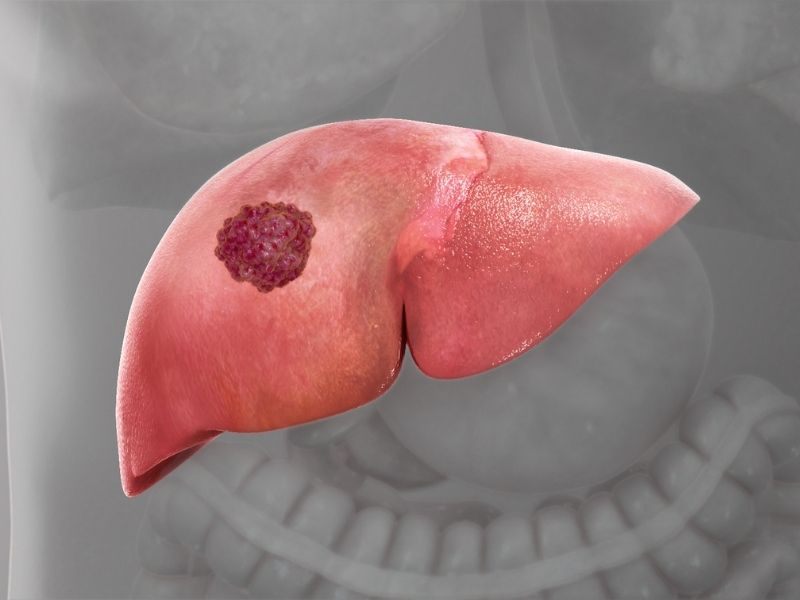

2. Nguy cơ ung thư gan và các vấn đề tiêu hóa liên quan

Rượu bia không chỉ gây tổn thương tế bào gan mà còn làm tăng nguy cơ ung thư gan khi sử dụng kéo dài. Bên cạnh đó, cồn kích thích niêm mạc dạ dày và ruột, làm tăng nguy cơ viêm loét, rối loạn tiêu hóa và hấp thu kém. Đây là một trong những tác hại của rượu bia thường bị xem nhẹ, nhưng lại ảnh hưởng trực tiếp đến chất lượng sống hằng ngày.

Rượu bia không chỉ gây tổn thương tế bào gan mà còn làm tăng nguy cơ ung thư gan